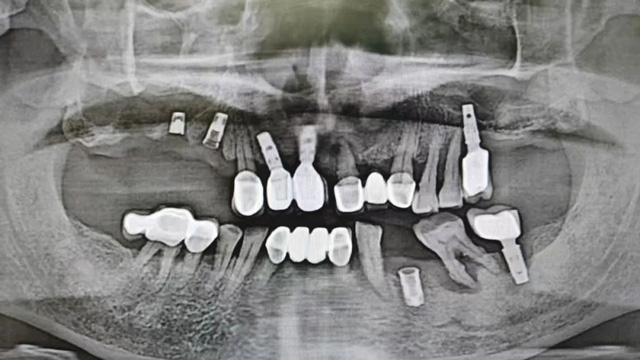

治疗前口腔全景片

“上面种了4颗,断了两颗,脱落1颗,只有1颗能用,下面有一颗牙冠脱落,另一颗有种植体周围炎,有明显的骨吸收。”吴叔叔剩下的天然牙也不好,做了几处修复,之前的牙冠修复用的都是烤瓷牙,有好几颗磨损严重露出了金属。由于存在缺牙、不良修复体等情况,口腔整体咬合紊乱,进食很困难。

经过检查,余国庆医生发现吴叔叔的口腔情况比较复杂。检查报告显示,他口腔里现存完整的种植牙只有两颗,上下颌各1颗。